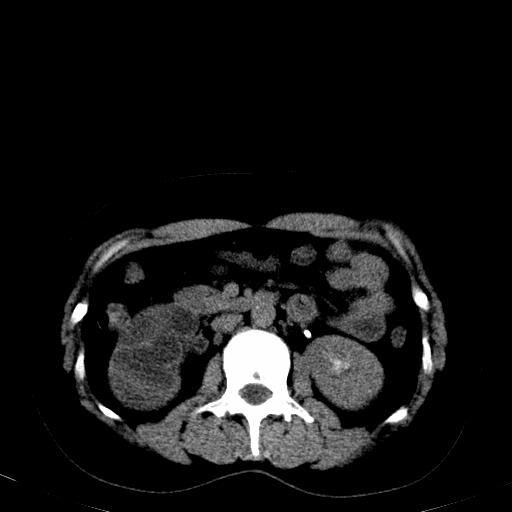

患者体检发现右肾体积增大,怀疑右肾积水

右肾多发囊肿,左肾、左输尿管结石

右肾重度积水,以肾盏积水明显,有分隔,上段输尿管轻度扩张,管壁增厚,考虑肾结核可能,请结合尿检查,胸部拍片排除肺结核。

右侧肾积水、左侧肾结石

右侧肾积水、左侧肾结石  ,要排除右肾结核可能。

右肾重度积水,建议ct向下扫描或逆行造影,左肾及左输尿管结石 .

1)不排除右肾结核可能。2)左肾及左输尿管上段结石?